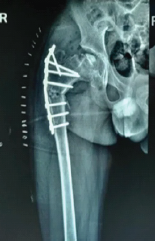

A Rare Case of Left Femoral Neck Fracture in a 6-Year-Old Boy with Osteopetrosis

Sri Harsha Reddy , J K Giriraj Harshavardhan , Sundar Suriyakumar , M Mohammed Tavfiq

………………………………p.216-219